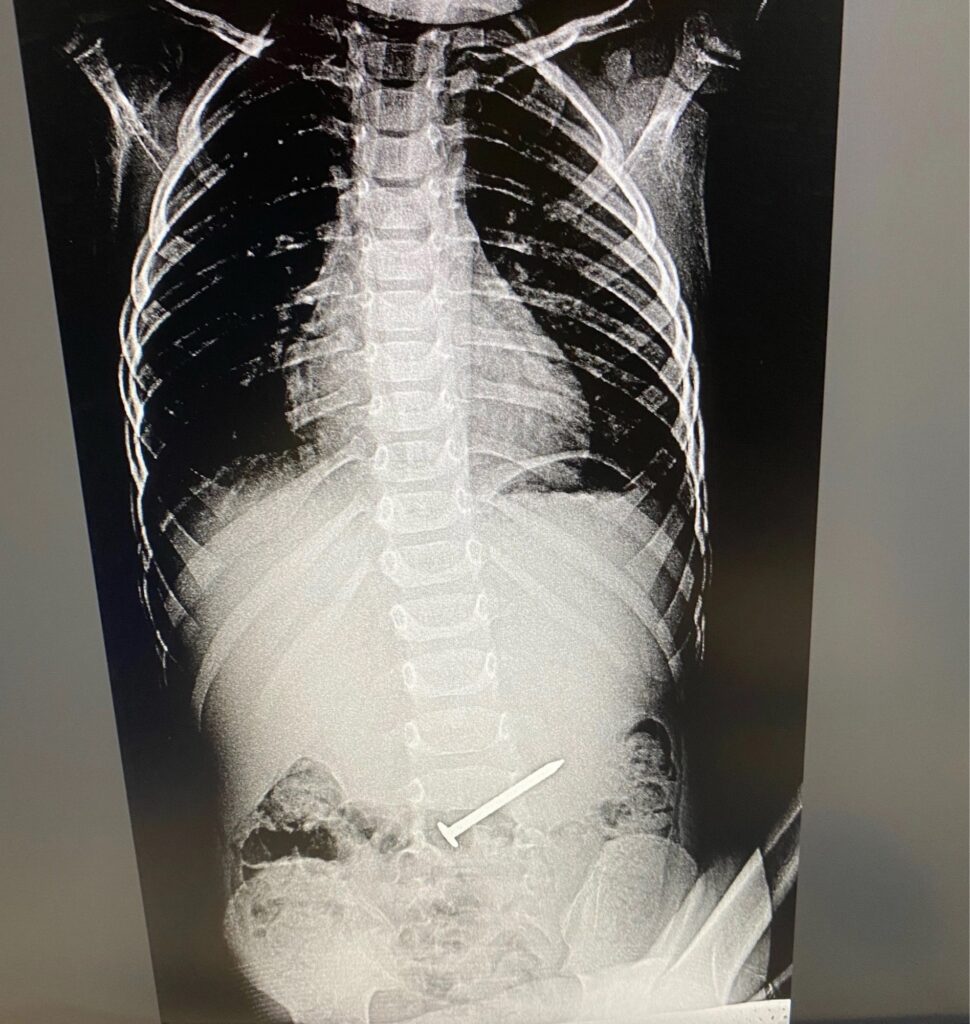

Фотография рентгеновского снимка, на котором поперек живота лежит огромный гвоздь, облетела недавно соцсети. ЧП произошло в Альметьевске с трехлетним мальчиком: во время игры он проглотил гвоздь и честно признался в этом маме, заверив, что живот у него не болит и гвоздь совсем не мешает.

Малыша привезли в детскую горбольницу, во время обследования выяснилось, что гвоздь находится в двенадцатиперстной кишке. Медики «выгнали» его в желудок, а затем достали.